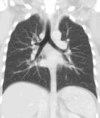

Lungs

A CT scan can be used for detecting both acute and chronic changes in the lung parenchyma, the tissue of the lungs.[41] It is particularly relevant here because normal two-dimensional X-rays do not show such defects. A variety of techniques are used, depending on the suspected abnormality. For evaluation of chronic interstitial processes such as emphysema, and fibrosis,[42] thin sections with high spatial frequency reconstructions are used; often scans are performed both on inspiration and expiration. This special technique is called high resolution CT that produces a sampling of the lung, and not continuous images.[43]

Bronchial wall thickening can be seen on lung CTs and generally (but not always) implies inflammation of the bronchi.[44]

An incidentally found nodule in the absence of symptoms (sometimes referred to as an incidentaloma) may raise concerns that it might represent a tumor, either benign or malignant.[45] Perhaps persuaded by fear, patients and doctors sometimes agree to an intensive schedule of CT scans, sometimes up to every three months and beyond the recommended guidelines, in an attempt to do surveillance on the nodules.[46] However, established guidelines advise that patients without a prior history of cancer and whose solid nodules have not grown over a two-year period are unlikely to have any malignant cancer.[46] For this reason, and because no research provides supporting evidence that intensive surveillance gives better outcomes, and because of risks associated with having CT scans, patients should not receive CT screening in excess of those recommended by established guidelines.[46]